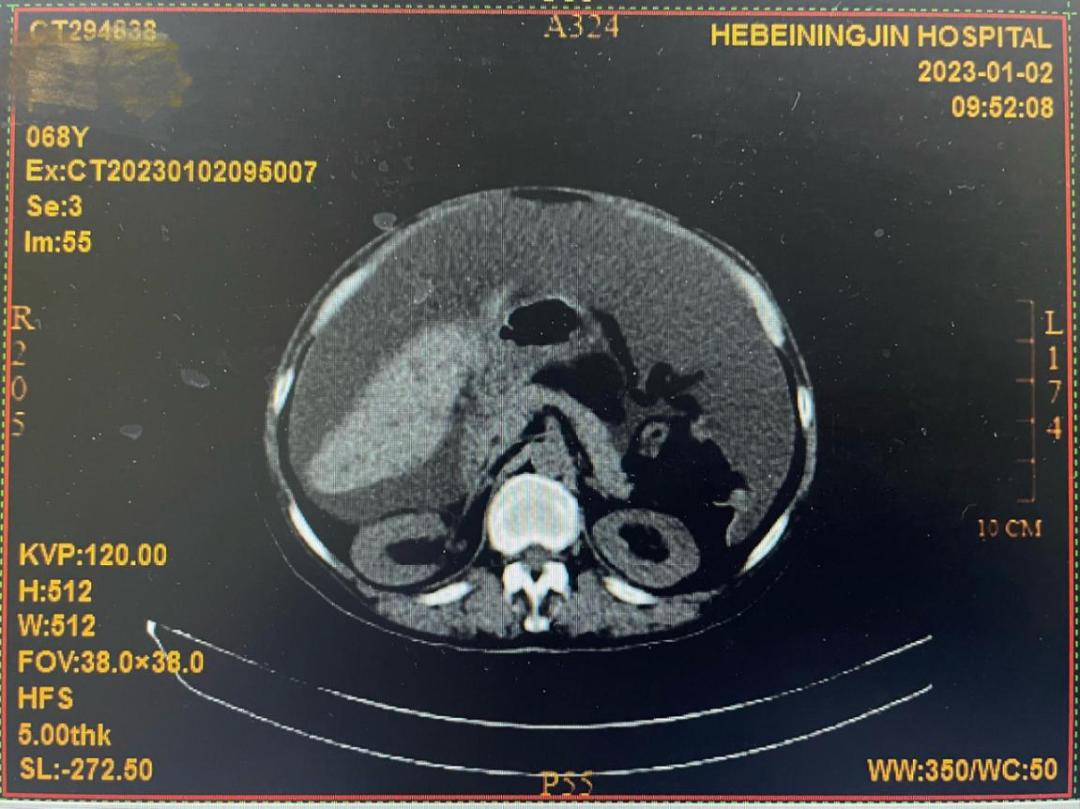

还有一位是68岁的患者文某,2021年初次来县医院肿瘤科就诊并确诊为胸膜恶性肿瘤;2023年1月因腹腔积液再次来院复诊,主管医师为其制定了个体化的化疗和热疗方案。一疗程后,CT显示腹水明显减少,患者主诉腹胀减轻。